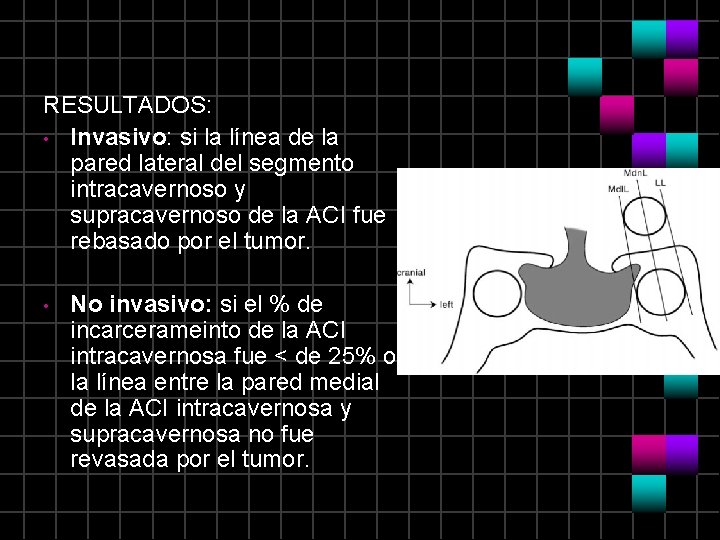

RESULTADOS: • Invasivo: si la línea de la pared lateral del segmento intracavernoso y supracavernoso de la ACI fue rebasado por el tumor. • No invasivo: si el % de incarcerameinto de la ACI intracavernosa fue < de 25% o la línea entre la pared medial de la ACI intracavernosa y supracavernosa no fue revasada por el tumor.